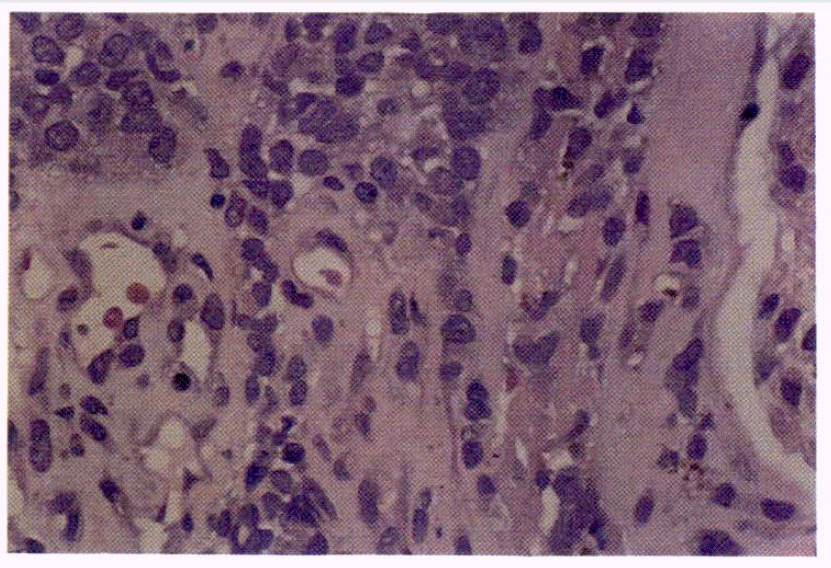

In February, 1986 she had been diagnosed as stage I malignant melanoma of the left cervical region which was treated with wide excision and left radical neck dissection. The pathologic report revealed it to be Clark’s level IV and 5 mm in thickness (Fig. 1). Since then she had been followed regularly through the outpatient department without any evidence of recurrence.

Fig. 1.

Superficial spreading melanoma, showing coalescent nests of malignant cells, is filling and expanding the papillary dermis and invading the reticular dermis (Clark level IV) (HE × 40)